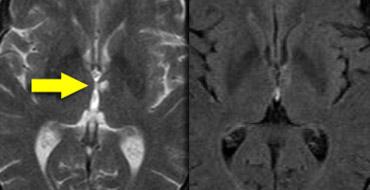

Bên trái là hình ảnh của một bệnh nhân bị huyết khối tĩnh mạch não sâu.

Lưu ý các vùng nhồi máu hai bên ở hạch nền.

Tiếp tục.

Không quan sát thấy khoảng trống dòng chảy (flow void) tại các tĩnh mạch não trong, xoang thẳng và xoang ngang phải (mũi tên xanh).

Trên hình MRA, xoang ngang phải không được hiển thị.